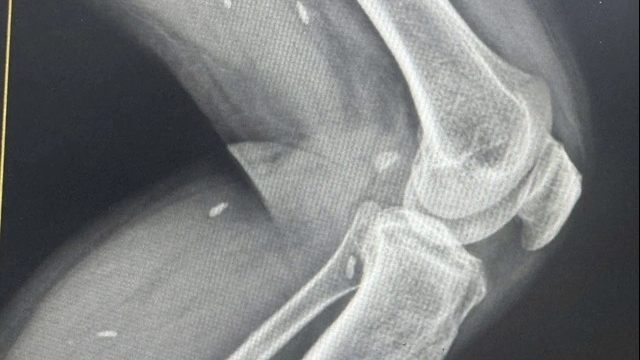

Điện dẫn truyền thần kinh – cơ: Kéo dài thời gian tiềm, giảm biên độ và giảm tốc độ dẫn truyền vận động các dây thần kinh chày sau và dây thần kinh mác sâu hai bên, phản xạ H hai bên mất.

| Hình ảnh đo dẫn truyền thần kinh chi dưới trước và sau điều trị |

Kết quả chụp cộng hưởng từ (MRI 3.0) Cột sống cổ: tủy cổ ngang mức C2-C6 có tín hiệu tăng trên T2W-I và T2W-W.